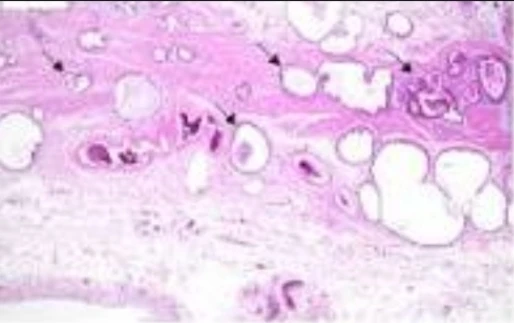

الكيمياء المناعية النسيجية: عدم استقرار الميكروساتلايت

الصورة التوضيحية المرتبطة بهذا التحليل